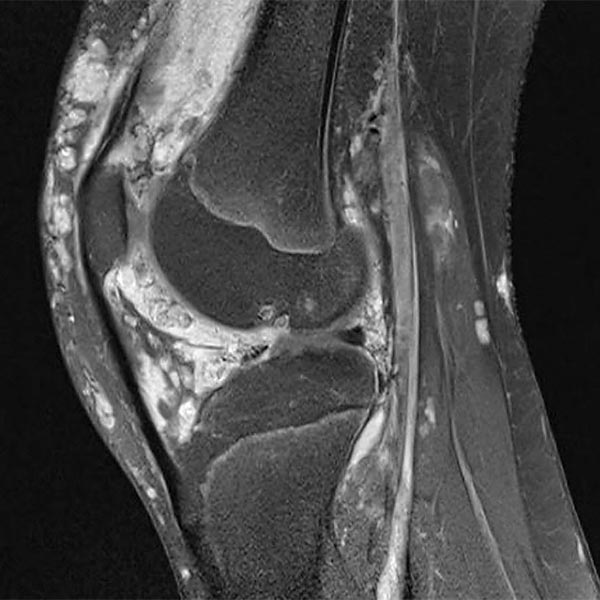

13-year-old girl with recurrent hemorrhages into the right knee joint due to an intra-articular venous malformation. As a result of the additional peri- and intra-articular thrombophlebitis and the cartilage damage that had occurred in the meantime, there was recurrent severe pain. First interventional treatment with sclerotherapy of the malformation and closure of the connections to the knee joint. Subsequently, removal of the synovium with surgical cartilage replacement planned.

Here, sagittal view of an MRI (T2-weighted with fat saturation) of the right knee. The venous malformation is clearly hyperintense (white in the image) and extends intra-articularly into the joint space. In addition, extensive cartilage damage.